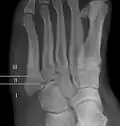

For several reasons, a Jones fracture may not unite. The diaphyseal bone (zone II), where the fracture occurs, is an area of potentially poor blood supply, existing in a watershed area between two blood supplies. This may compromise healing. In addition, there are various tendons, including the fibularis brevis and fibularis tertius, and two small muscles attached to the bone. These may pull the fracture apart and prevent healing.

Zones I and III have been associated with relatively guaranteed union and this union has taken place with only limited restriction of activity combined with early immobilization. On the other hand, zone II has been associated with either delayed or non-union and, consequently, it has been generally agreed that fractures in this area should be considered for some form of internal immobilization, such as internal screw fixation.

These zones can be identified anatomically and on x-ray adding to the clinical usefulness of this classification.[21] Surgical intervention is not, by itself, a guarantee of cure and has its own complication rate. Other reviews of the literature have concluded that conservative, non-operative, treatment is an acceptable option for the non-athlete.[22]

-

Anatomy of the fifth metatarsal. -

3 zone description -

2 zone description